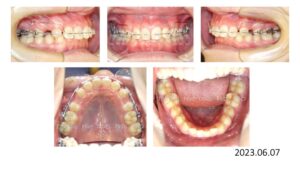

次の症例は叢生です。

50歳の女性です。娘さんがうちで治療した数年後、自分も歯並びを治したいと希望され、治療を開始しました。

上下両側4番抜歯後、上下顎にブラケットを付け、

スペースクローズが終わり、細部の仕上げを行い、

治療期間 2年 7か月で動的治療を終了しました。

人前で笑えるようになりました、と、とても喜んで頂く事が出来ました。